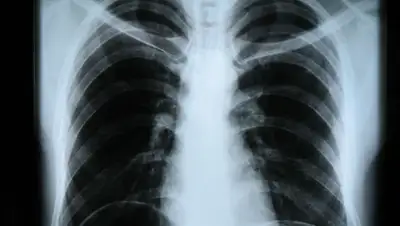

Госпитализировать с пневмонией могут не только по результатам КТ, но и рентгена

Цифровых рентген-томографов в десятки раз больше, чем аппаратов КТ.

Цифровых рентген-томографов у нас в десятки раз больше, чем КТ, поэтому более доступны - не только в столице, но и в каждом районном центре такие аппараты стоят. Эти протоколы мы сейчас оформим, чтобы был была возможность необязательно проходить КТ для того, чтобы лечь в стационар и понять, болеете вы пневмонией или нет, - заключил глава Минздрава.